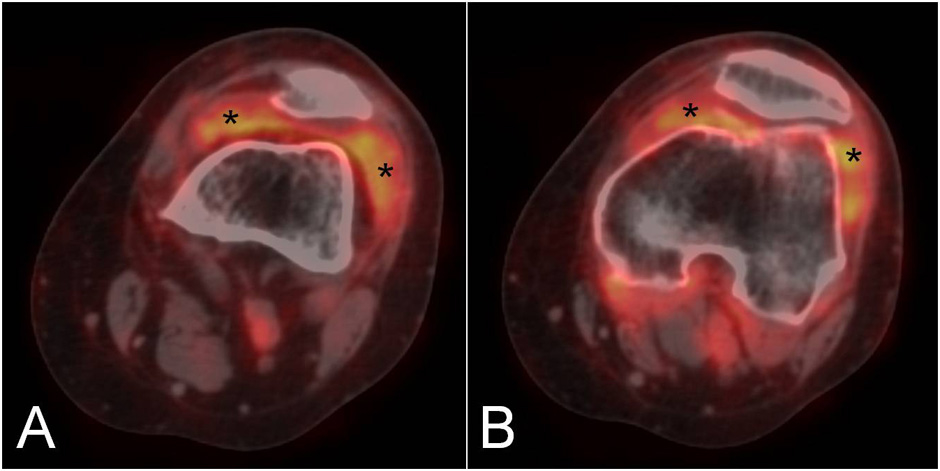

Figure 3

The coronal (A) and axial (B) PET/CT fused images of the wrist in a patient with rheumatoid arthritis demonstrate a focal area of F18-FDG uptake in the carpal tunnel, suggestive of flexor tendons tenosynovitis (asterisk). Tracer uptake is also observed in the metacarpophalangeal joints (C, arrows).

Although the main applications of PET and PET/CT are in the fields of oncology, neurology, psychiatry, and cardiology [47], novel data suggest a possible role of these techniques in rheumatology [4]. The main application is the diagnosis and follow-up of large vessel vasculitis [49, 50]. More recently RA patients have also been studied with this technique and their disease activity has been evaluated by calculating the standard uptake value (SUV) in the affected joints [51]. This method has allowed the measurement of a total score that includes all the joints involved by RA in a panoramic view of the patient. It has shown a good correlation with clinical evaluation and has also revealed involvement of the atlanto-axial joint in a few asymptomatic patients [52]. In another study, the results of PET imaging of the rheumatoid knee were in agreement with those obtained by more traditional imaging techniques, such as DCE-MRI and US [53]. In particular, PET uptake was significantly correlated with all MRI enhancement parameters as well as with synovial membrane thickness measured by US. PET uptake correlated with CRP and serum concentrations of metalloproteinase-3. After treatment with a single infusion of infliximab, an anti-TNFα biological agent, total SUV, MRI and laboratory findings significantly decreased [54]. Other anecdotal observations have confirmed the potential role of PET in the evaluation of treatment efficacy in RA patients by studying the wrist after etanercept administration [55]. One of the limitations of this method is that spatial resolution is low and imaging often suboptimal for small joints. Nevertheless, studies on hand and foot joints have been performed in RA with satisfying results [56]. Figures 2 and 3 show the results of PET/CT examination of the knee and hand, respectively, in patients with RA. In addition, PET/CT could be used for differential diagnosis between RA and seronegative spondyloarthritides (SpA) [57] especially by demonstrating a different anatomical pattern of uptake between these diseases. Evaluation of images of PET/CT scans of the shoulder, hip and knee joints have shown that FDG accumulated at the entheses in SpA and in the synovium in RA patients. In general, the main advantage of PET/CT examination in arthritis is the possibility of calculating a global score of the amount of inflammation present in the joints. A clear drawback is that, due to the high amount of ionising radiation, it cannot be used in repeated follow-up examinations. To reduce radiation exposuree, PET/CT could be used to obtain functional and morphological information at baseline, and PET alone could be repeated over time.